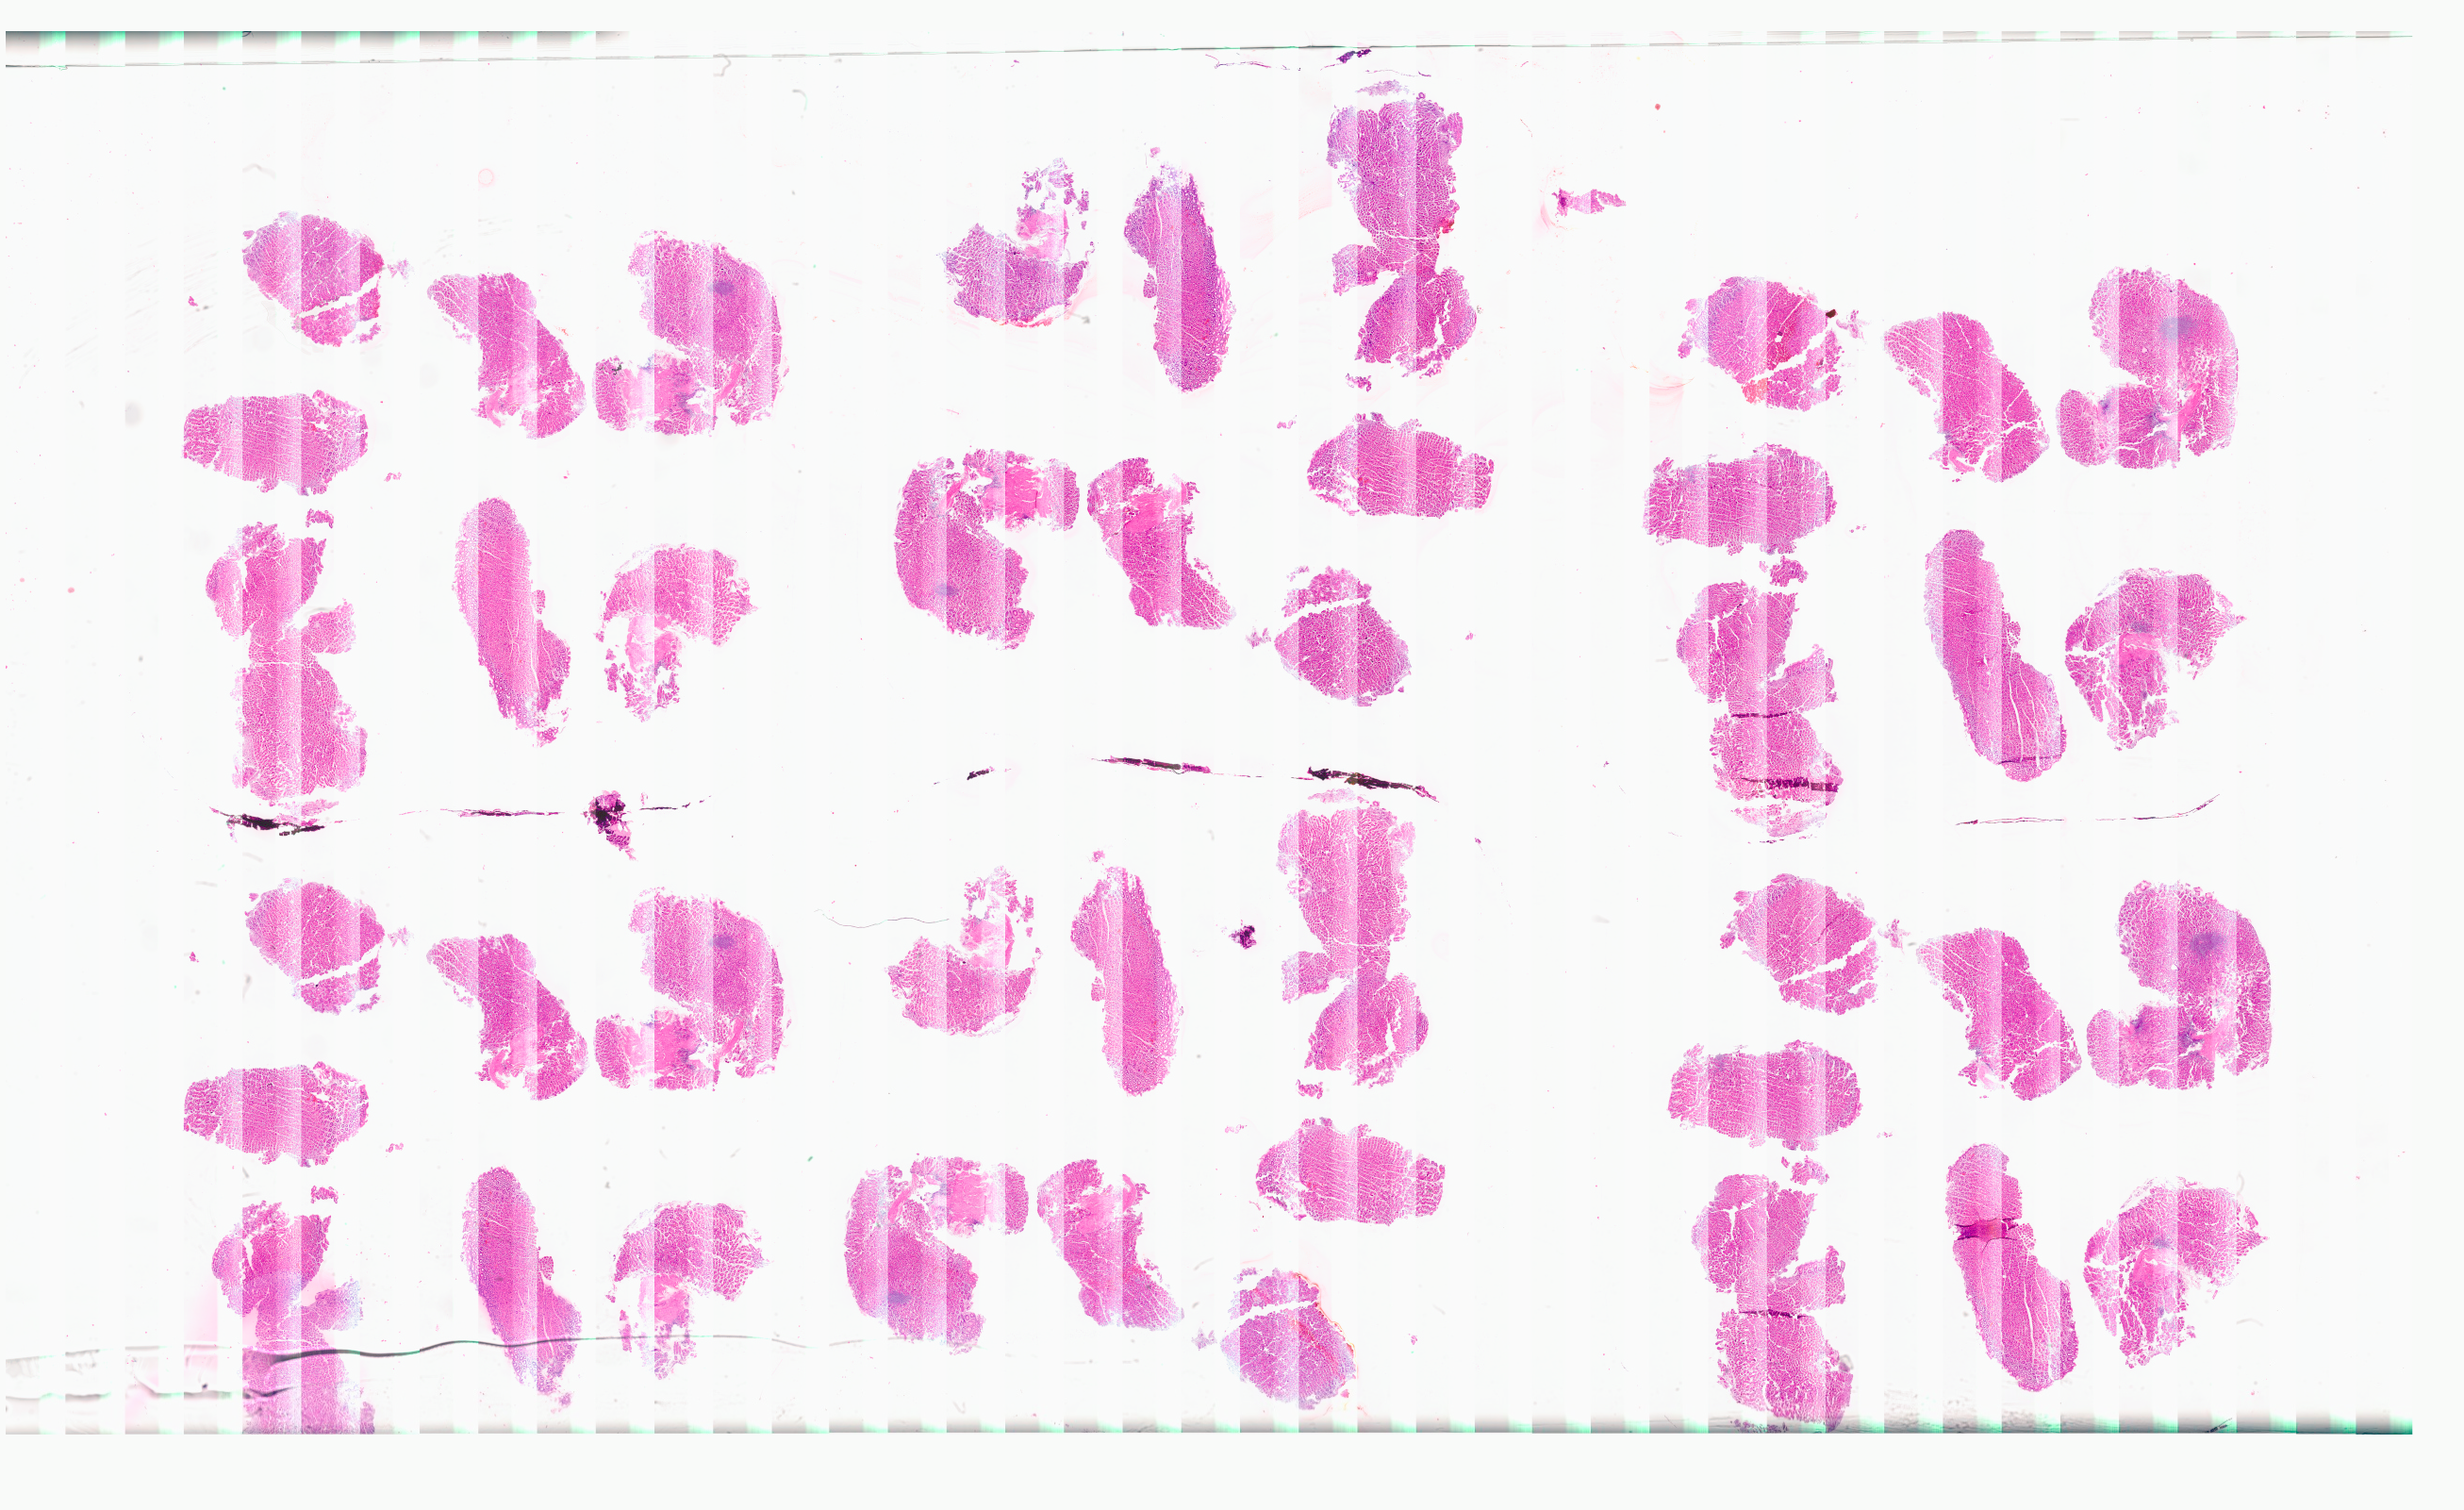

Örnek Rutin Vakalar

patolojiatlasi.com